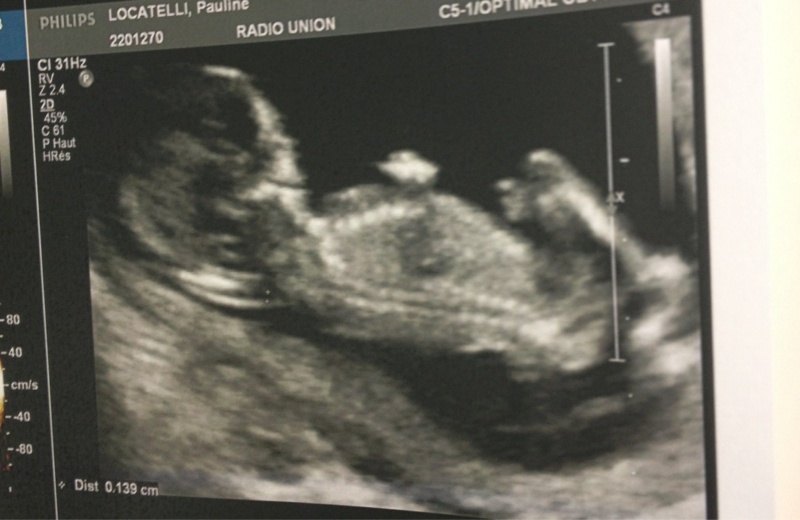

bébé pour l'été 2014 ;)

Voila

Dis moi ce que tu en penses ( j'ai que sa)

lol je vien de ressortir les echo de Nohlan pour voir comment ca fesai mais la honnetement je ne vois rien... a nohlan jai vraiment vu le kiki tout de suite (le gyneco l'a meme pris en photo lol) et a ma derniere echo on a vu egalement un kiki et ce qui va avec lol donc la je ne serai pas d'une bonne aide desole ma poulette

cest vrai que cest pas super comme photo mais apres niveau qualité ça va encore, pour bien voir y a pas mieux que la 3D mais bon financièrement faut suivre aussi...